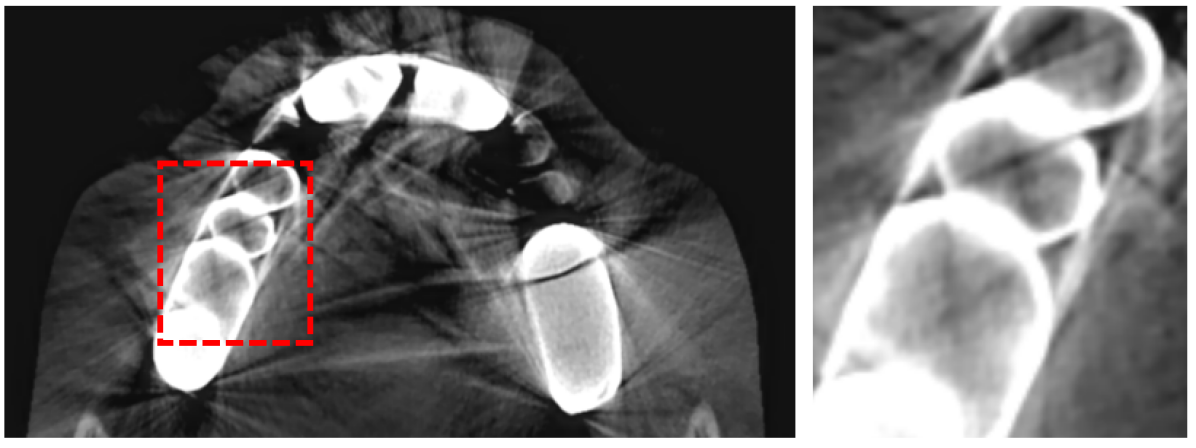

Digitized orthodontic applications in dentistry have increased based on the development of cone beam computed tomography (CBCT) imaging. CBCT is a widely used medical imaging technique that provides high resolution 3D volumetric data. To build an effective computer-aided diagnosis system in orthodontic applications, such as oral treatment planning for tooth reformation and implant guide simulation, automatic segmentation of individual teeth from the CBCT images is an essential prerequisite (Fig. 1). However, accurate segmentation of an individual tooth from a CBCT image is a challenging task owing to heterogeneous intensity distribution, unclear boundaries between the tooth root and alveolar bone (Fig. 2a), and diverse shapes and poses. Moreover, the majority of CBCT images contain severe metal artifacts that hinder the accurate segmentation of teeth (Fig. 2b). In this study, we propose a fully automated instance segmentation framework using 3D images of teeth that is robust to several challenging conditions of the teeth, such as, dynamic poses, missing teeth, inter-tooth proximity, and presence of severe metal artifacts.

To employ a CNN for individual tooth segmentation, we chose the instance segmentation framework. Unlike other organs in medical imaging, such as liver or spleen, there are multiple instances of a tooth in a single CBCT image. Thus, individual tooth segmentation requires an instance segmentation technique rather than semantic segmentation, which is performed through preceding object detection. The primary challenges of individual tooth detection and segmentation arise from: 1) high overlapping ratio between instances (i.e., teeth) and 2) the existence of severe metal artifacts in CBCT images. These two primary issues degrade the accuracy of the individual tooth segmentation task.

Finally, we applied a 2mm margin, i.e., dilation, to each axis of the output boxes to compensate for a possible inaccurate detection. We resized the realigned image to for all inputs of the network. The performance of the tooth detector can be improved significantly by image realignment and VOI cropping to reduce the overlapping ratio of an object. It is clear that reducing the inter-overlapping area boosts the NMS performance for true example mining (i.e., sampling), which leads to accurate region detection. Moreover, the tooth-to-volume ratio significantly increased through VOI realignment; thus, our proposed framework runs without a patch-wise input cropping procedure [11], which was previously proposed to resolve the problems that arise from anchor-based methods for small objects. The comparative experiments and ablation studies are described in Section \Romannum4.

The manual seeded level-set methods [6, 7] demonstrate inferior performances while segmenting teeth with predominant metal artifacts (Table II). The energy-based (i.e., level-set function) algorithmic approach failed while defining an optimum stopping criterion (Fig. 12b). The AJI measures for level-set methods are omitted because the box detectors do not exist in the level-set-based methods. In particular, the low precision and sensitivity values indicate that level-set methods have over-segmented or under-segmented the teeth in many cases (Figs. 12b and 13a). The accuracies of the Mask-RCNN [17] and ToothNet [11] showed comparable performance to the level-set-based methods. The instance segmentation framework successfully detected and segmented the teeth automatically. However, it failed to detect all the teeth regions accurately, which resulted in a degradation of the segmentation performance. Moreover, the performance of the segmentation itself also showed low accuracy owing to the metal artifacts (Figs. 12c and 12d). Figure 13 illustrates the more severe conditions of metal artifacts. The performance of the detection and segmentation processes significantly degraded in ToothNet [11] (Fig. 13b) and Mask-RCNN [17] (Fig. 13c). Conversely, our proposed method outperformed the other state-of-the-art methods (Figs. 12e and 13d); further, the comparison between the PA- and non-PA-based results also demonstrated that the employment of a PA detector significantly improved the proposed architecture (Table II). The superior AJI value clearly shows that successful detection improved the overall performance.